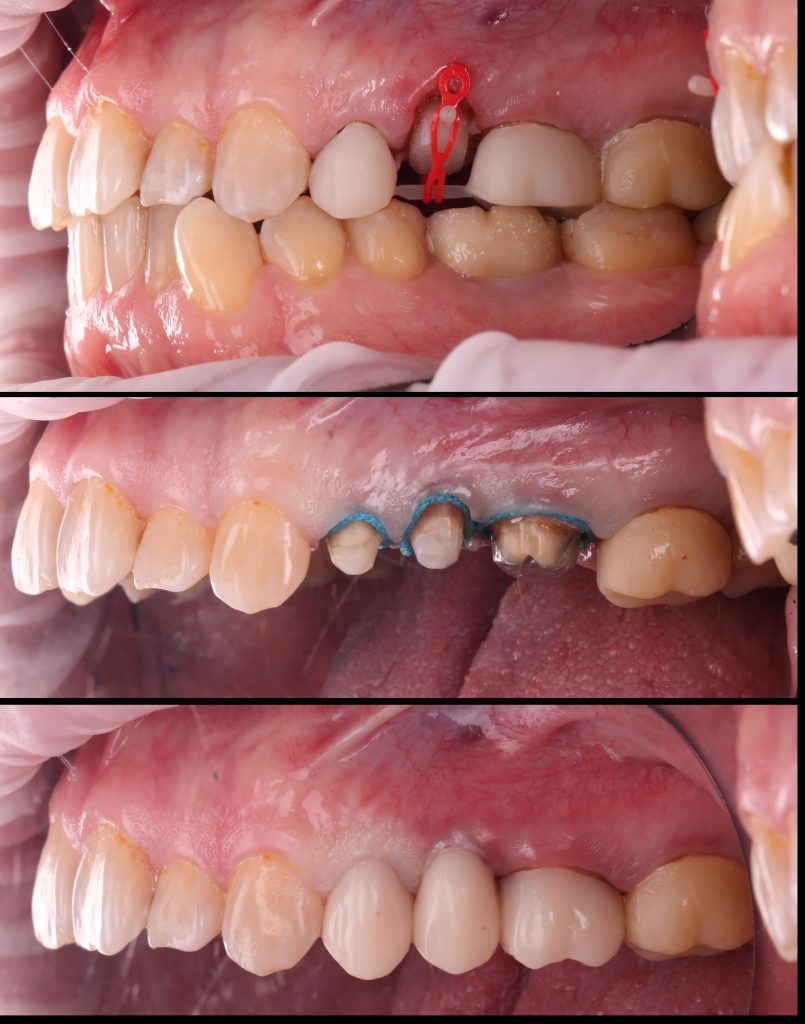

Поведено эндодонтическое лечение

Был получен достаточный объём твердых тканей над уровнем десны, что обеспечило создание феррул-эффекта. Первый этап ортопедической реабилитации завершен фиксацией временных конструкций